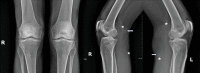

Synovial osteochondromatosis is a rare benign pathology arising from the synovial membrane of the joints, synovial sheaths or uncommonly the bursae around the joints. Baker's cysts are fluid filled, synovium-lined lesions arising in popliteal fossa. Synovial chondromatosis involving the Baker`s cyst is extremely rare. The aim of this case report is to document this exceedingly rare extra articular synovial pathology involving Baker's cysts of bilateral knees and to emphasize the importance of radiographs and sonography in the diagnosis.